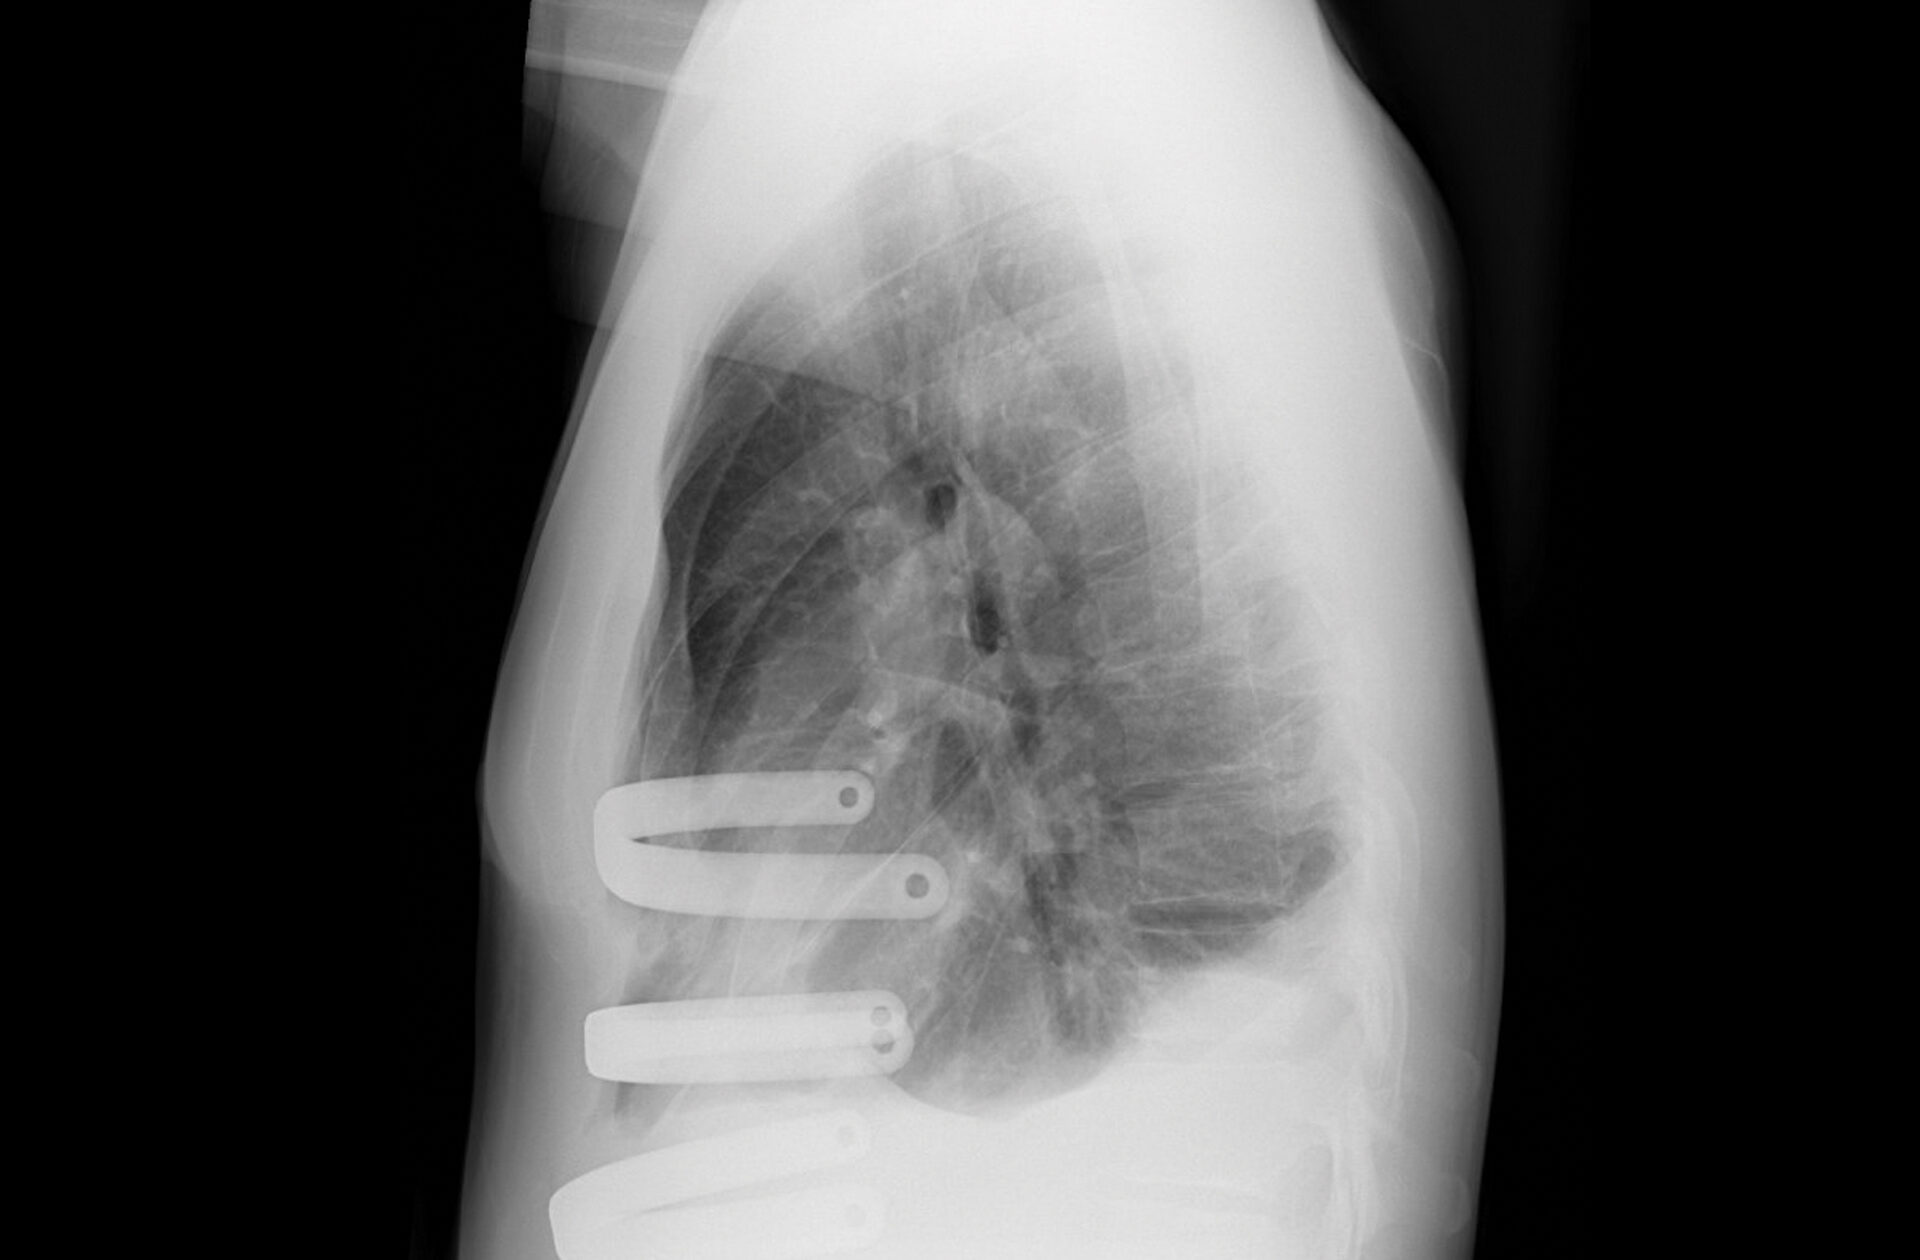

Sagittal view of the patient’s pectus excavatum. Source: NYU Langone Health